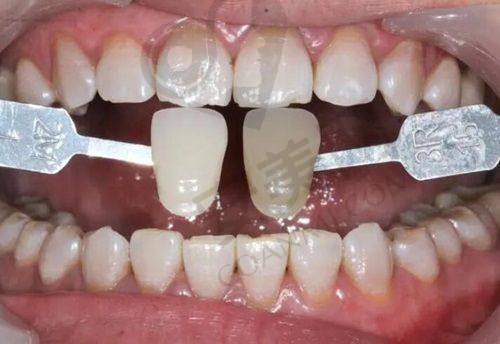

此外,牙冠、补牙等项目价格也较为合理,树脂补牙200元起/颗;国产烤瓷冠980元起/颗;爱尔创全瓷牙冠1280元起/颗;根管治疗1180元起/颗;牙齿贴面3600元起/颗。而且医院还会举办一些优惠活动,如全口种植牙有高达9千的优惠,暑期戴时代天使牙套矫正龅牙价格只要1w + 等。